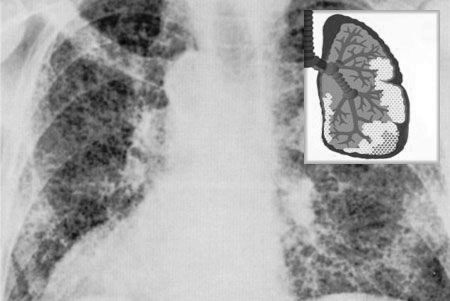

Фіброз легенів фото рентген